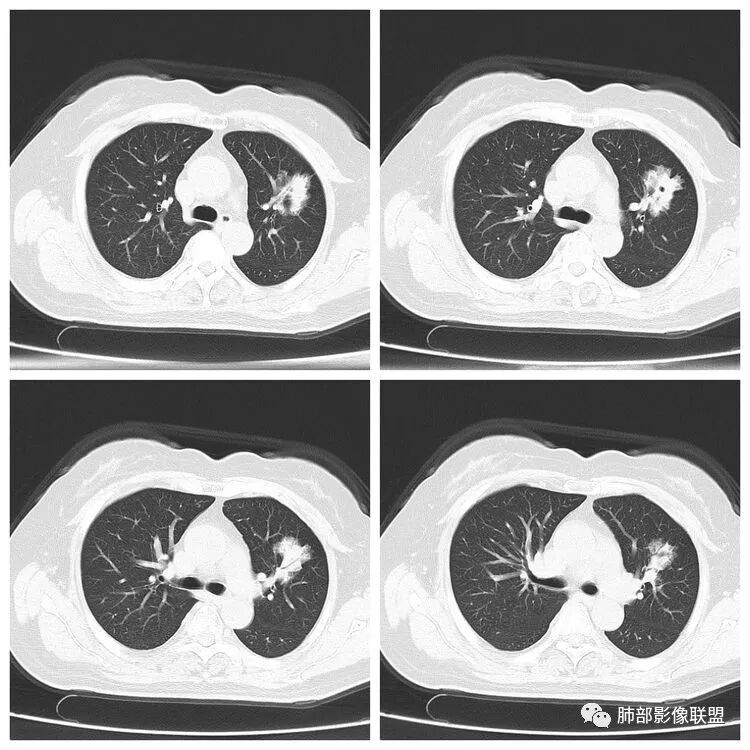

以下是两个时间点左右对比

2019.11.26  👇                           2020.01.20👇                                            2019.11.26片

2020.01.20片

2.早期CT表现左肺上叶不规则团块影,呈混合密度,以实性密度为主,但整体密度偏低,周围隐约见磨玻璃密度影。

边缘不规则,前内侧缘见小叶间隔限制(注意,并非典型深分叶),病灶外侧细长毛刺,病灶内有小空泡及空气支气管征,有胸膜牵拉征象。

上述征象均提示病灶为恶性病灶,但边缘特征及空气支气管征似乎有别于常见的浸润性腺癌及MALT。